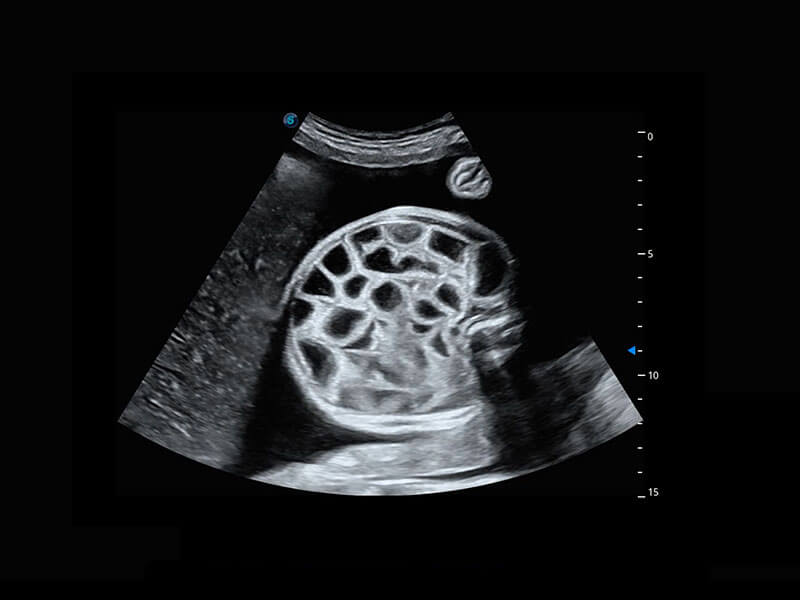

P60为盆底超声检查提供应用方案,多种腔内及腹部容积探头提供从二维、三维到四维的优异图像品质,实时快速三维容积数据获取,专业的测量工具包等人性化设计,为超声医生诊断提供有力保障。

Lev.Hiat A-r: 16.33 cm2

Lev.Hiat H-r: 53.70 mm

Lev.Hiat W-r: 43.96 mm

Lt-LUG-r: 24.16 mm

Rt-LUG-r: 19.94 mm

能够简化盆底检查的操作流程,可在二维模式及三维成像模式下实现一键自动提取出标准切面、自动识别当前切面、自动测量,提升盆底检查的高效性,同时也能让青年医生快捷的获得准确的检查结果。